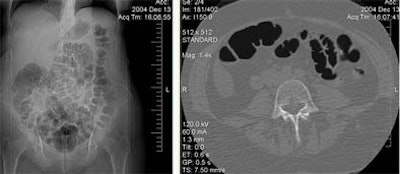

![]() |

| A 65-year-old woman underwent follow-up VC following a right colectomy for colon cancer. The intervention three years earlier included removal of the ileocecal valve with subsequent ileocolic anastomosis. Insufflation in the supine decubitus did not cause abdominal pain. At VC the colon was normal but shows overdistension of the small bowel in the supine CT data (above) and confirmed in the prone CT data (below). Objective or subjective symptoms were not reported. Immediately after prone decubitus positioning, at the end of the exam, the patient reported headache, nausea, and stimulus to vomiting. Cold sweat and diaphoresis were also observed. All images courtesy of Dr. Emanuele Neri. |